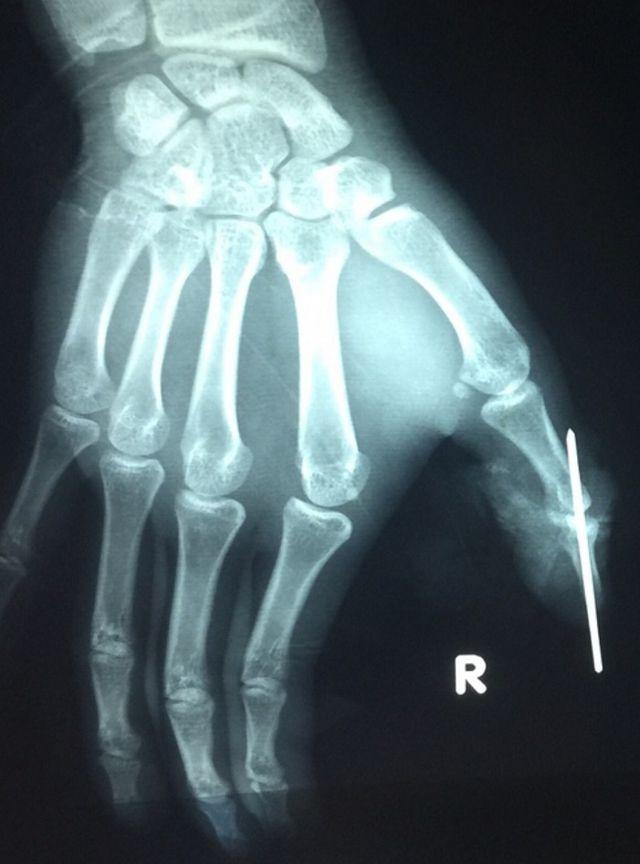

Ê kíp đã tiến hành cắt lọc hoại tử; kết hợp lại xương; dùng kĩ thuật "siêu vi phẫu" nối động mạch đốt xa ngón cái (đường kính động mạch ở vi trí này nhỏ dưới 1mm); nối thần kinh và tĩnh mạch ngón cái; nối lại gân để đảm bảo vận động cho bệnh nhân.

Sau cuộc vi phẫu, đốt ngón bị đứt lìa được tưới máu tốt, hiện ngón tay đã sống lại. Bệnh nhân được tiếp tục theo dõi để tránh nguy cơ nhiễm trùng, hoại tử. Bác sĩ nhận định sau khi bình phục, các chức năng ngón tay cái bị đứt của bệnh nhân sẽ không bị ảnh hưởng nhiều.